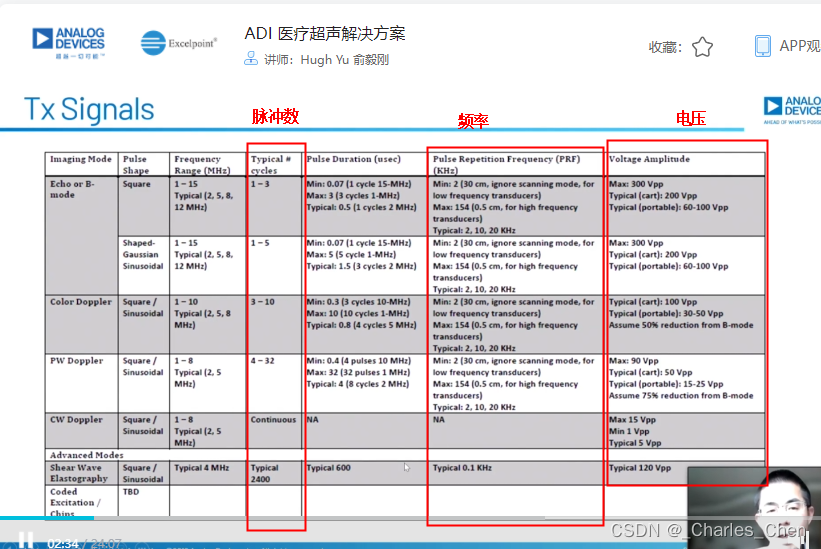

数字发射波束成形器用于产生所要求的数字发射信号,以正确的时间和相位生成聚焦发射信号。高性能超声系统可通过任意波形发生器产生复杂的发射波形,从而优化图像质量。这些情况下,发射波束成形器以大约40MHz速率生成8位至10位数字字符,并以此产生所要求的发射波形。数/模转换器(DAC)将数字波形转换成模拟信号,通过线性高压放大器进行放大,用于驱动传感器单元。由于这种发射技术占用较大体积,而且价格昂贵、需要消耗较高能量,所以,这种架构只限于昂贵的非便携设备。多数超声系统并不使用这种发射波束成形技术,而是采用多级高压脉冲发生器产生需要发射的信号。在这种替代方案中,利用高集成度、高压脉冲发生器快速切换传感器单元至适当的可编程高压电源,产生发射波形。为了产生一个简单的两极发射波形,脉冲发生器需要交替地将传感器单元切换到由数字波束成形器控制的正、负发射电压。更复杂的设计可以让传感器单元切换至多路电源和地,从而产生更复杂、性能更好的多重波形。

近几年,随着二次谐波成像的广泛应用,高压脉冲发生器对于斜率和对称性的要求越来越高。二次谐波成像利用了人体的非线性声学特性。这些非线性特性倾向于将频率fo的声能转变成2fo频率。多种原因使得接收二次谐波信号能够获得更高的图像质量,因此,二次谐波成像得到了广泛应用。

二次谐波成像有两种基本的实现方法。一种称为标准谐波成像,尽可能抑制发射信号的二次谐波,从而使接收到的二次谐波主要源于人体的非线性。这种模式要求二次谐波的发射能量至少低于基波能量50dB。所以,发射脉冲的占空比要求是准确的50%且误差小于±0.2%。另一种方法称为脉冲反相,利用反相后的发射脉冲产生同一图像路径的相位相反的两路接收信号。在接收器中对这两路反相接收信号求和,恢复由于人体非线性产生的谐波信号。这种脉冲反相的方法必须在叠加时尽可能抵消发射脉冲的反相成分。所以,高压脉冲发生器的上升时间和下降时间必须严格一致。

多数的心脏检查和一些通用的超声成像系统中,常常使用连续波多普勒CWD以确保精确测量心脏内高速流动的血液。CWD模式下,超声传感器单元以传感器孔径为中心分割成对等的两部分。一半单元用于发射,产生CWD聚焦波束;另一半单元用于接收,产生聚焦的接收波束。发射单元的驱动波形为多普勒频率的方波,频率范围通常为1MHz至7.5MHz。发射波形的抖动必须足够小,以防止相位噪声对多普勒频移检测的影响。通过正确调整发射波形的相位,实现发射波束聚焦。类似地,通过正确调整接收波形的相位并进行叠加,实现CWD接收信号聚焦。在此模式下,发射和接收同时进行,有用的多普勒信号频率和不移动的人体组织在发射基波频率下产生的强反射信号的频率相差只有几kHz。处理如此大的信号所需要的动态范围已经超出了图像接收通道VGA、AAF和12位ADC可以承受的范围。因此,CWD必须使用其它高动态范围接收解决方案。